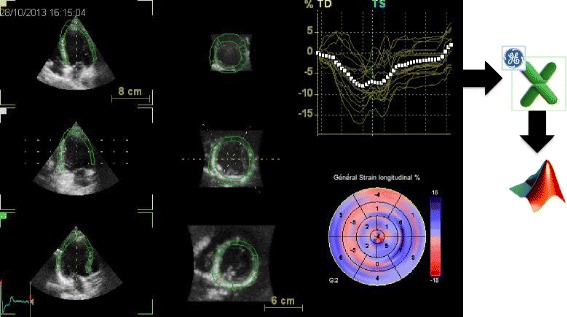

Fig. 1.

LV dataset display with 3D speckle-tracking analysis of longitudinal myocardial deformation, using the 4D–AutoLVQ package (EchoPAC version 110.1.3, GE Healthcare, Horten, Norway). Microsoft Excel files of 3D longitudinal strain analyses were exported for dedicated analysis performed, with Matlab software (Mathworks Inc., USA)